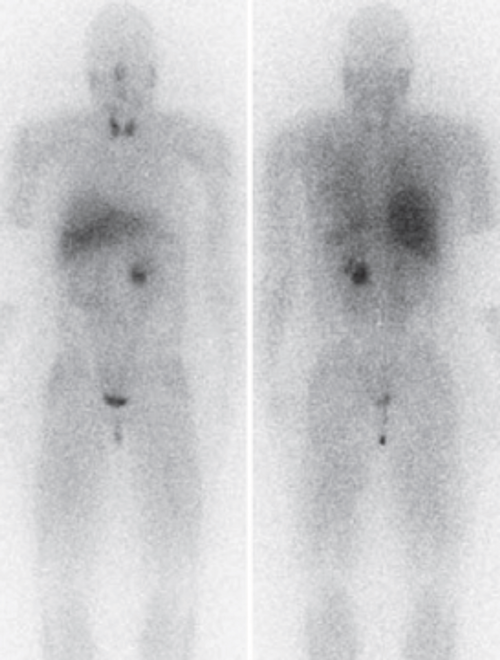

A 35-year-old woman presented to her GP feeling unwell and was found to have an elevated blood pressure of 170/115mmHg. The GP arranged a scan of the abdomen that showed a 3cm adrenal lesion. She is referred to your clinic urgently for review with a suspected phaeochromocytoma.

- In view of these risks you perform the shown scan. What is this scan and what does it show?

-

Nuclear medicine metaiodobenzylguanidine (MIBG) scan. Demonstrates a left phaeochromocytoma with no further adrenal or extra-adrenal lesions.

Initially needs alpha blockage, with long acting phenoxybenzamine to manage blood pressure. Beta blockers (propranolol) can then be started to prevent cardiac arrhythmias. She will need to be well hydrated preoperatively. Surgically there should be minimal manipulation on the adrenal gland, with early division of the adrenal vein.